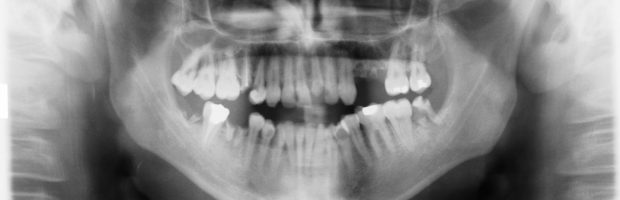

Digital X-Rays (digital radiography) is the most advanced form of dental X-Rays. Rather than using X-Ray film, this technique utilizes an electronic sensor that captures the digital image for storage on a computer. This is much faster than making film images, and digital images can be instantly viewed, enlarged, manipulated and transmitted, thereby enabling the dentist and dental hygienist to more readily detect and define problems. Digital X-Rays offer the additional benefit of reducing radiation by 80 to 90% when compared to the relatively low exposure generated by traditional dental x-rays.

Dental X-Rays are important diagnostic tools that are essential in enabling dental professionals to correctly prescribe preventative and corrective treatments. They provide valuable information that would not otherwise be available during regular dental exams. Information provided by digital dental X-Rays make it possible for dentists and dental hygienists to safely and accurately detect and diagnose hidden dental abnormalities—a necessary first step in developing an appropriate plan of treatment. Without the benefit of Digital X-Rays, problems may go undetected until they have become severe.

As a minimum, new patients should always have a full mouth series of dental X-Rays. Barring complications, a full mouth series is generally considered good for three to five years. Bite-wing x-rays (x-rays that show top and bottom teeth biting together) are generally taken at regular check-up visits. They are recommended at least once or twice per year to detect new / developing dental problems.